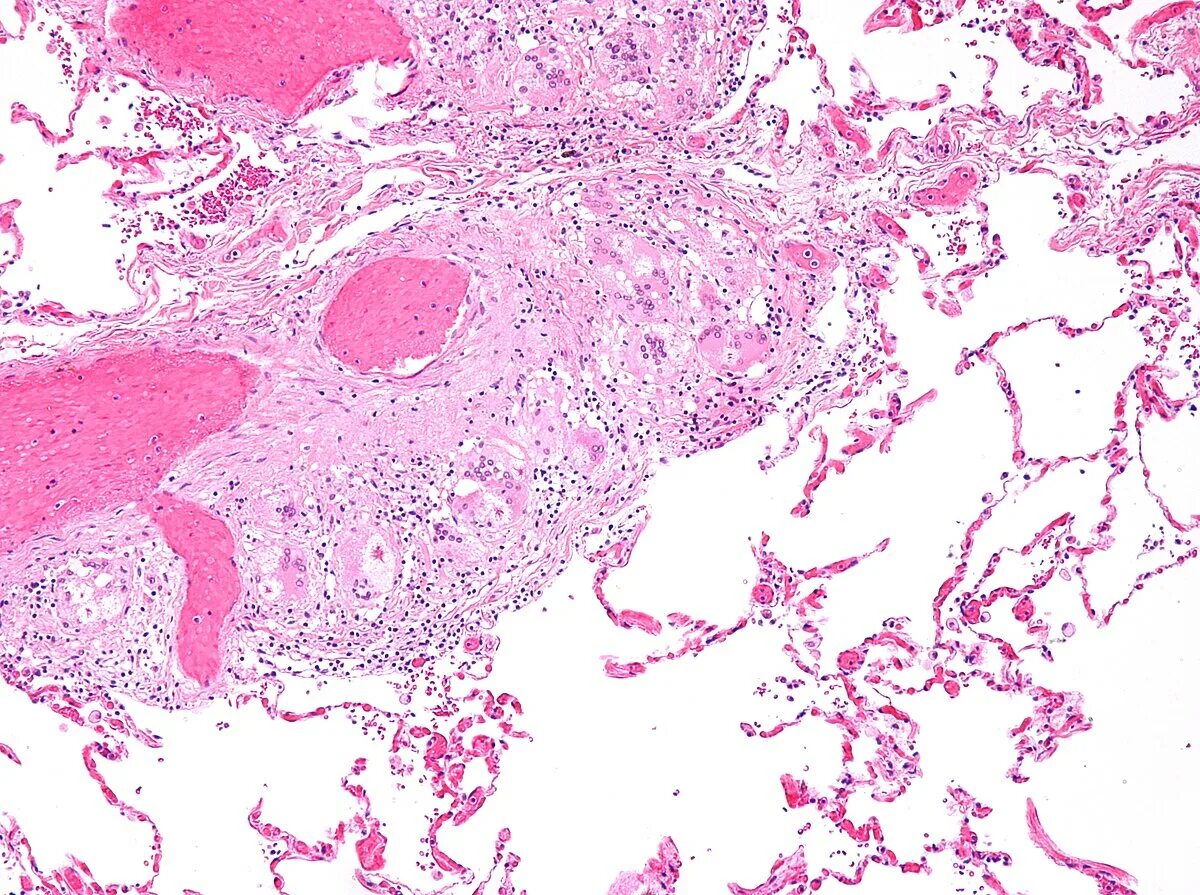

Клетка типа инородных тел